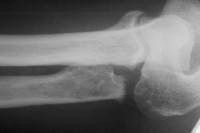

In this case, a significant length of ulna was removed. A longitudinal groove was made in the ulna and marked with ink prior to oblique osteotomy to aid confirmation of alignment for fixation.

As might be expected, the ends of the ulna could not be easily brought together.repositioning of the distal ulna segment required an extensive exposure as detailed in

this other case.